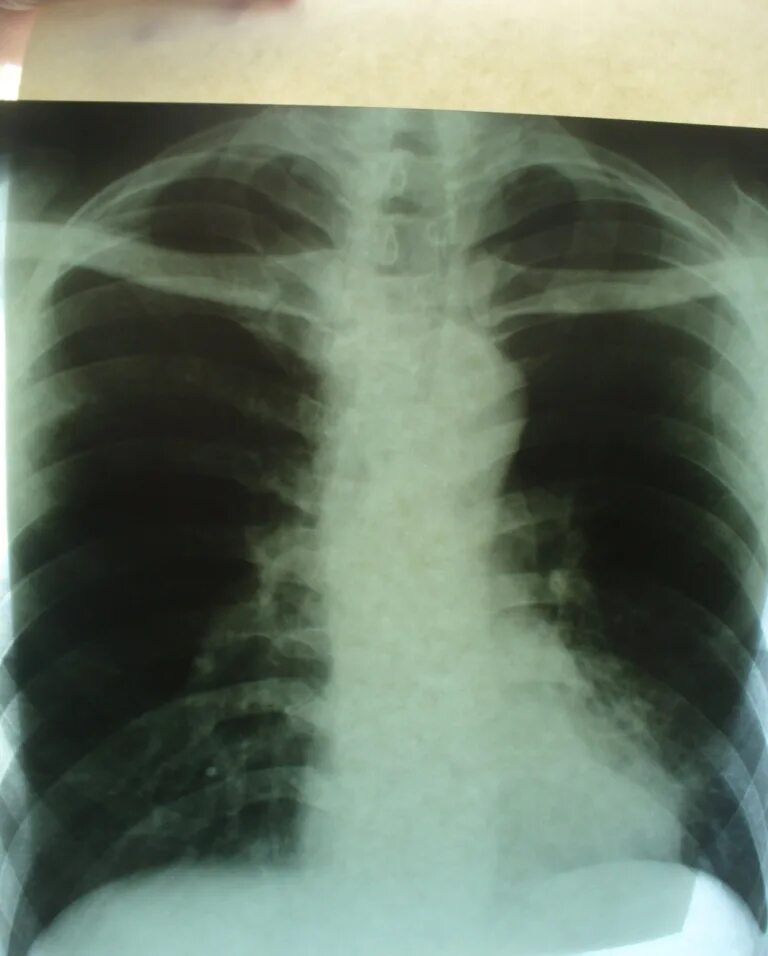

Стадия инфильтрации легких